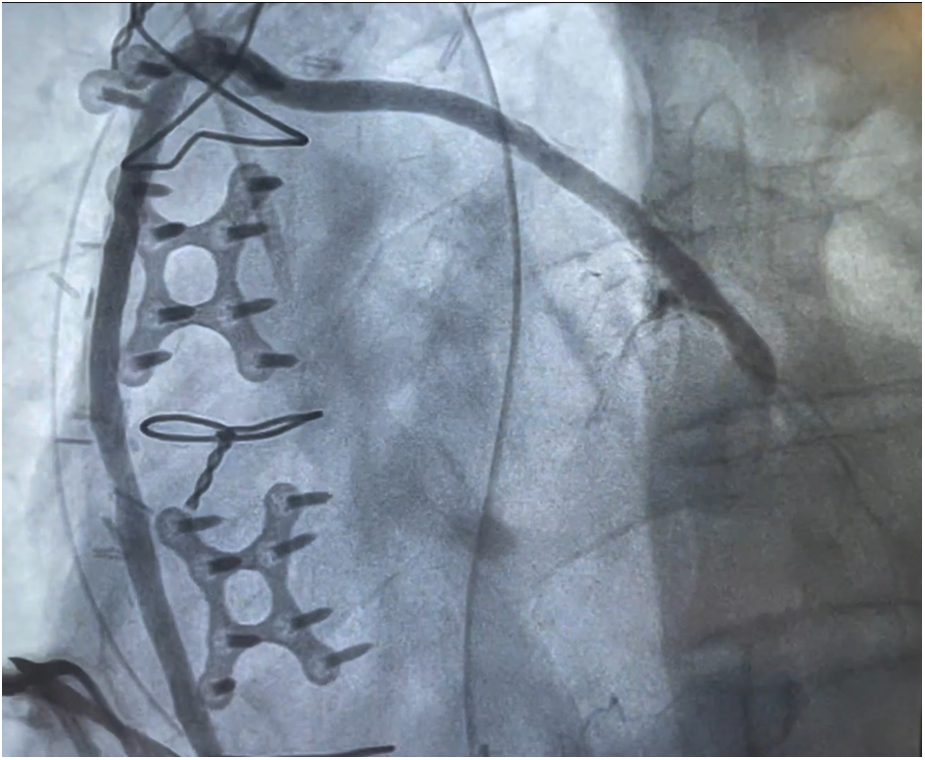

Figure 3

Postoperative angiographic visualization of the piggyback proximal anastomosis.

3.1 Primary endpoints

Two (1.8%) patients required ventilation longer than 24 h. Importantly, no strokes or myocardial infarctions occurred, and only one (0.9%) patient needed surgical re-exploration for bleeding. The mean length of hospital stay was 5.5 [4.0–8.0] days. At 30 days, no patient died or required repeat revascularization. Cardiac readmission occurred in 3 (2.7%) patients, Table 3. Patients who underwent postoperative angiography demonstrated no evidence of thrombosis, occlusion, kinking, or torsion of the piggyback anastomoses (Figure 3). Furthermore, the feasibility of angiographic assessment of the piggyback technique was confirmed, as interventional cardiologists experienced no difficulties in identifying or injecting the piggyback proximal anastomosis during the procedure. At a mean follow-up of 1.0 [0.5–1.7] years, there were no cardiac-related deaths, with an overall survival of 98.2% (110/112). Only one myocardial infarction occurred (0.9%), and four strokes (3.6%) were reported. In this regard, one stroke occurred in a patient with a known arteriovenous malformation that eventually ruptured, and one confirmed after a subsequent percutaneous coronary intervention, thus not directly related to the CABG surgery or anastomotic technique. Repeat Piggyback revascularization rate was 3.6% (4/112) at a mean of 2.0 ± 0.5 years. Among the revascularized grafts, three were veins and one was an artery. As far as the piggyback configuration of these patients who underwent percutaneous interventions, revascularization was performed on two grafts attached directly to the aorta and two grafts placed on top of the first graft, thus showing that repeat revascularization is independent of the piggyback configuration, Table 4.